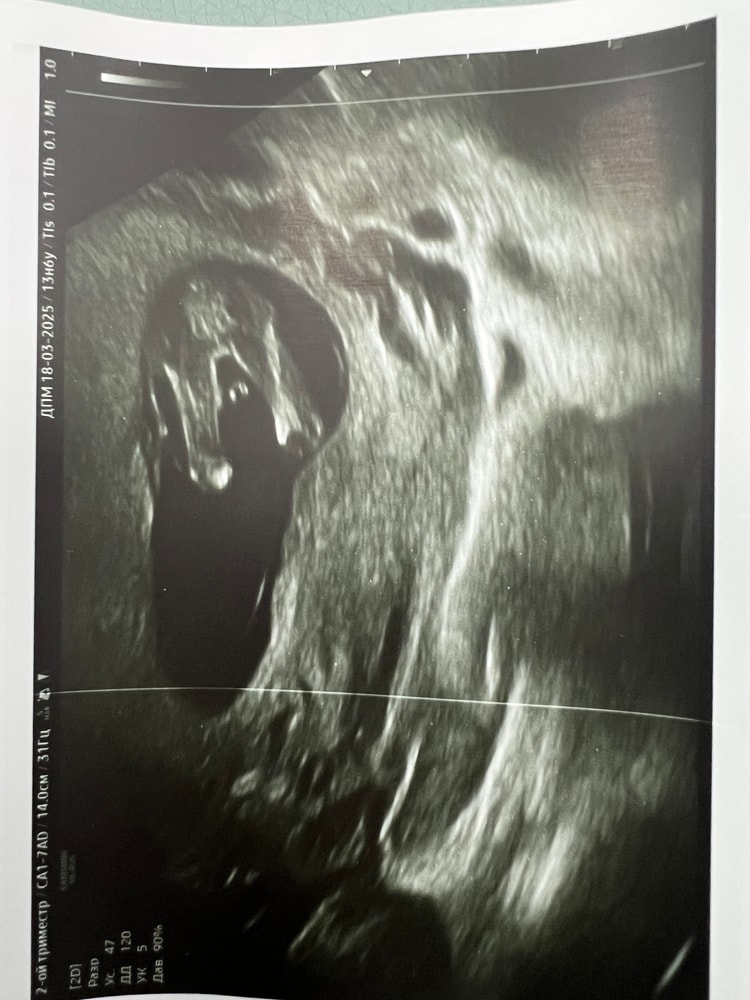

Пол малышаВсем привет! Очень волнует вопрос, какого же пола малыш) На фото 16 недель и 5 дней, была платно у врача она показала прям вот нашего мальчика. В ЖК сказали что кажется девочка, но толком не посмотрели, смотрели только длину матки.

Как можно на таком сроке не сказать точно и вон как ребенок показывает им всё😂